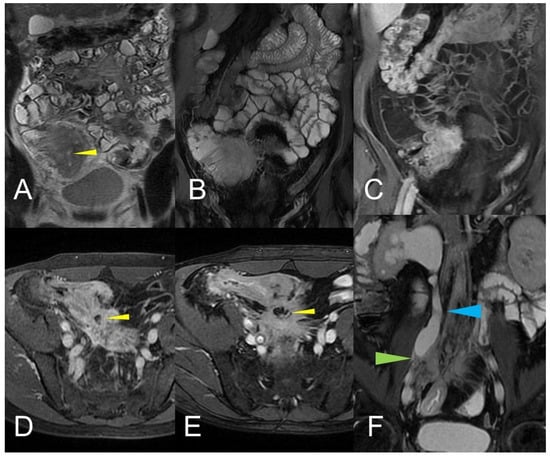

Figure 14.

Large climbing inflammatory conglomerate. A small abscess is evident in the center of the inflammatory conglomerate (yellow arrowheads in (A,D,E)). It shows marked enhancement (yellow arrowhead in (C)) and determines conspicuous retracting effects both on the mesentery (spiculate aspect in (D,E)), in which it develops, and on the adjacent loops. In this patient, the right distal pelvic ureter is also narrowed, (green arrowhead in (F)) with hydronephrosis (blue arrowhead in (F)). (A): coronal T2-weighted MRE image; (B,F): coronal fast imaging employing steady-state acquisition (FIESTA) image; (C): coronal contrast-enhanced fat-suppressed T1-weighted image; (D,E): axial contrast-enhanced fat-suppressed T1-weighted image.